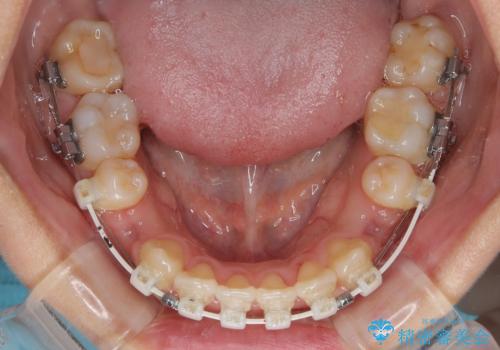

急速拡大装置 狭い骨幅を拡大した上で、口元の突出感を改善する抜歯矯正治療

単純に上下左右の第一小臼歯4本を抜歯して口元の突出感を改善することも考えられましたが、上顎骨よりも下顎骨の幅が広いため、より良い咬み合わせを達成することを目的として、急速拡大装置を用いて上顎骨を拡大することとしました。

歯列矯正では基本的に骨格を改善することはできませんが、急速拡大装置(MARPE)を使用することで上顎骨を側方に拡大させることができ、咬合状態を大きく改善することができます。